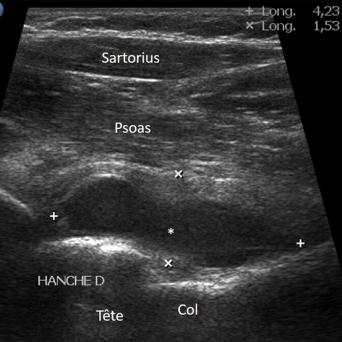

L’image

du jour

Illustration

Cancer de la prostate

Le « Movember » – qui se déroule chaque mois de novembre – a pour but de sensibiliser la population à la lutte contre les cancers masculins, dont le cancer de la prostate qui est en première position (26,5 % des cancers chez les hommes de plus de 65 ans).